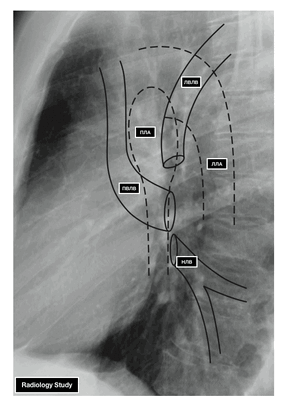

ЛЕГОЧНЫЕ ВЕНЫ

Из капилляров легкого начинаются венулы, которые сливаются в более крупные вены и в каждом легком формируют по две легочные вены.

Из двух правых легочных вен больший диаметр имеет верхняя, так как по ней оттекает кровь от двух долей правого легкого (верхней и средней). Из двух левых легочных вен больший диаметр имеет нижняя вена. В воротах правого и левого легких легочные вены занимают их нижнюю часть. В задней верхней части корня правого легкого расположен главный правый бронх, кпереди и книзу от него — правая легочная артерия.

- ЛВЛВ — левая верхняя легочная вена

- ПВЛВ — правая верхняя легочная вена

- НЛВ — нижняя легочная вена

- ПЛА — правая легочная артерия

- ЛЛА — левая легочная артерия

У левого легкого сверху находится легочная артерия, кзади и книзу от нее — левый главный бронх. У правого легкого легочные вены лежат ниже артерии, следуют почти горизонтально и на своем пути к сердцу располагаются позади верхней полой вены, правого предсердия и восходящей части аорты. Обе левые легочные вены, которые несколько короче правых, находятся под левым главным бронхом и направляются к сердцу также в поперечном направлении, кпереди от нисходящей части аорты. Правые и левые легочные вены, прободая перикард, впадают в левое предсердие (их конечные отделы покрыты эпикардом).